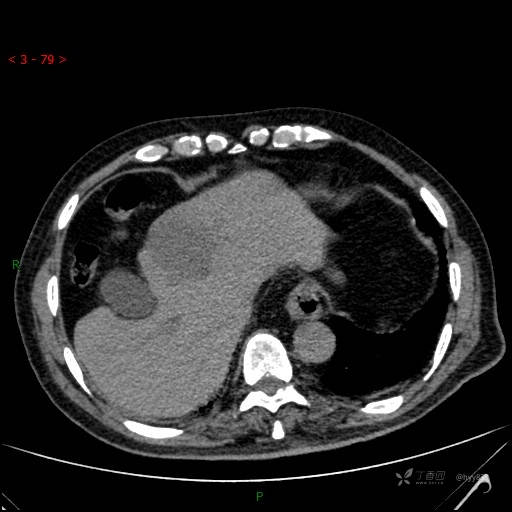

肝脏CT平扫

img